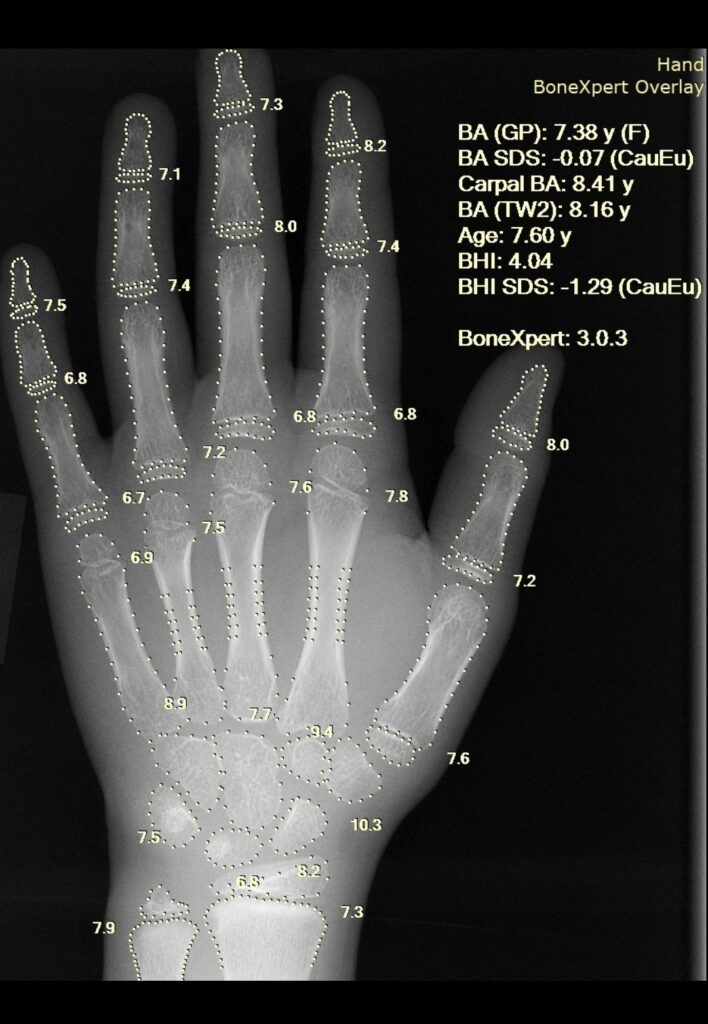

Bone age, on the other hand, tells us how mature the child’s bones are behaving biologically. It is usually estimated using an X-ray of the hand and wrist, where doctors look at how developed the bones and growth plates appear.